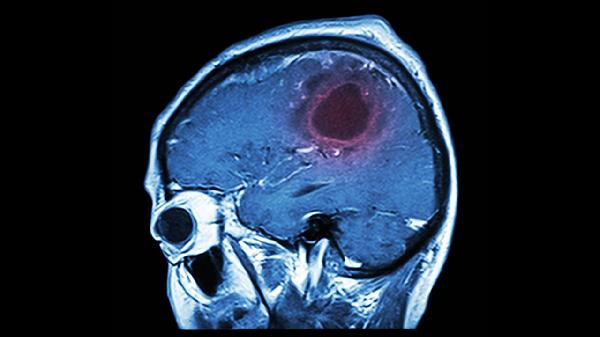

脑溢血后肌张力管理需药物与康复并重,除规范用药外应坚持关节活动度训练、神经肌肉电刺激等物理治疗。饮食注意补充优质蛋白如鱼肉、豆制品促进神经修复,控制钠盐摄入避免血压波动。定期复查头颅CT评估出血吸收情况,出现肌痉挛加重或药物不耐受时及时调整方案。康复期保持情绪稳定,家属协助记录症状变化以优化治疗。